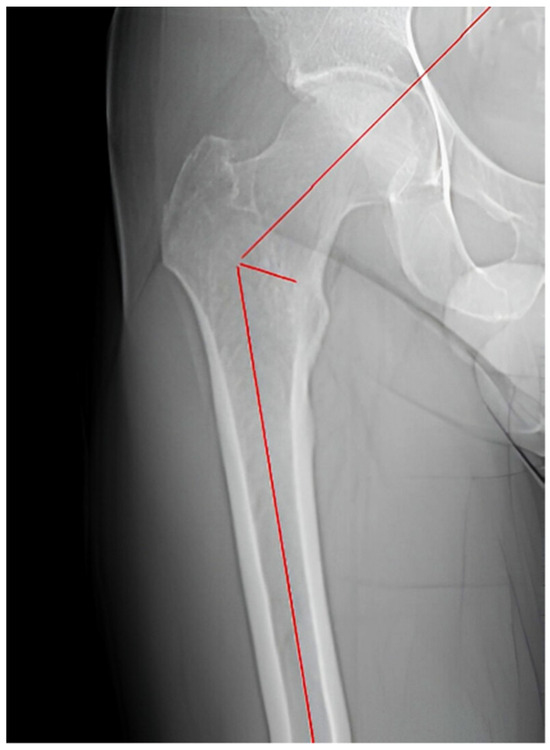

2.2. Measurements

| Femoral Inclination | 128.46° ± 7.16° (127.22°–129.70°) | 129.95° ± 6.86° (128.61°–131.29°) | 0.107 |